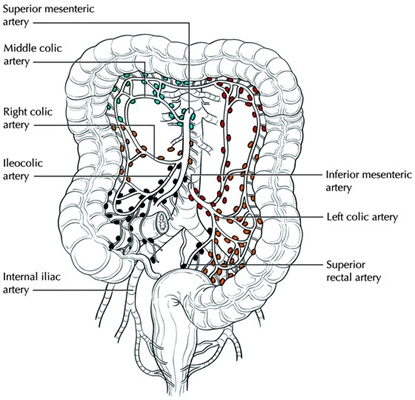

盲腸的位置 (50)

盲腸的位置 (6)

盲腸的位置 (7)

盲腸的位置 (8)

盲腸的位置 (9)

盲腸的位置 (46)

盲腸的位置 (47)

盲腸的位置 (48)

盲腸的位置 (49)

盲腸的位置 (5)

盲腸的位置 (42)

盲腸的位置 (43)

盲腸的位置 (44)

盲腸的位置 (45)

盲腸的位置 (41)

盲腸的位置 (40)

盲腸的位置 (30)

盲腸的位置 (31)

盲腸的位置 (32)

盲腸的位置 (33)